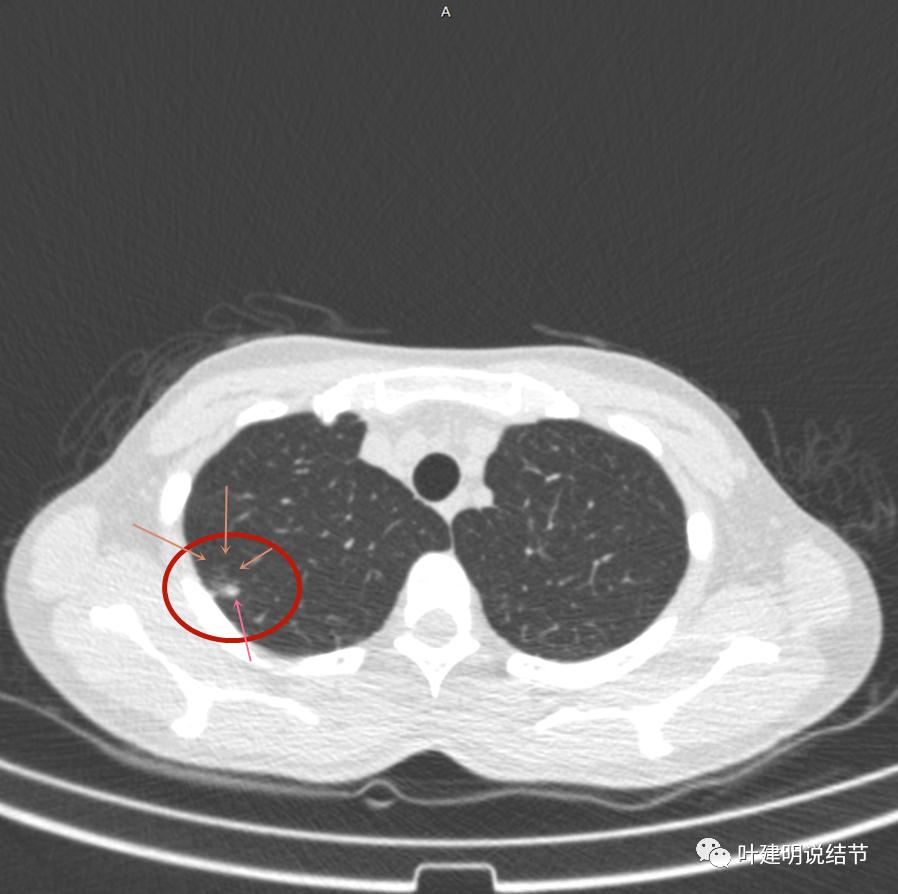

主病灶不见了的层面,仍有边上高密度条索状的影像,邻近胸膜仍有异常(蓝色箭头)

影像初印象:右上病灶散在,不致密,密度偏高,磨玻璃影不是平时典型恶性的磨玻璃瘤肺边界清楚或含毛刺征的征象,更符合炎性病变,且邻近胸膜广基的异常增厚。